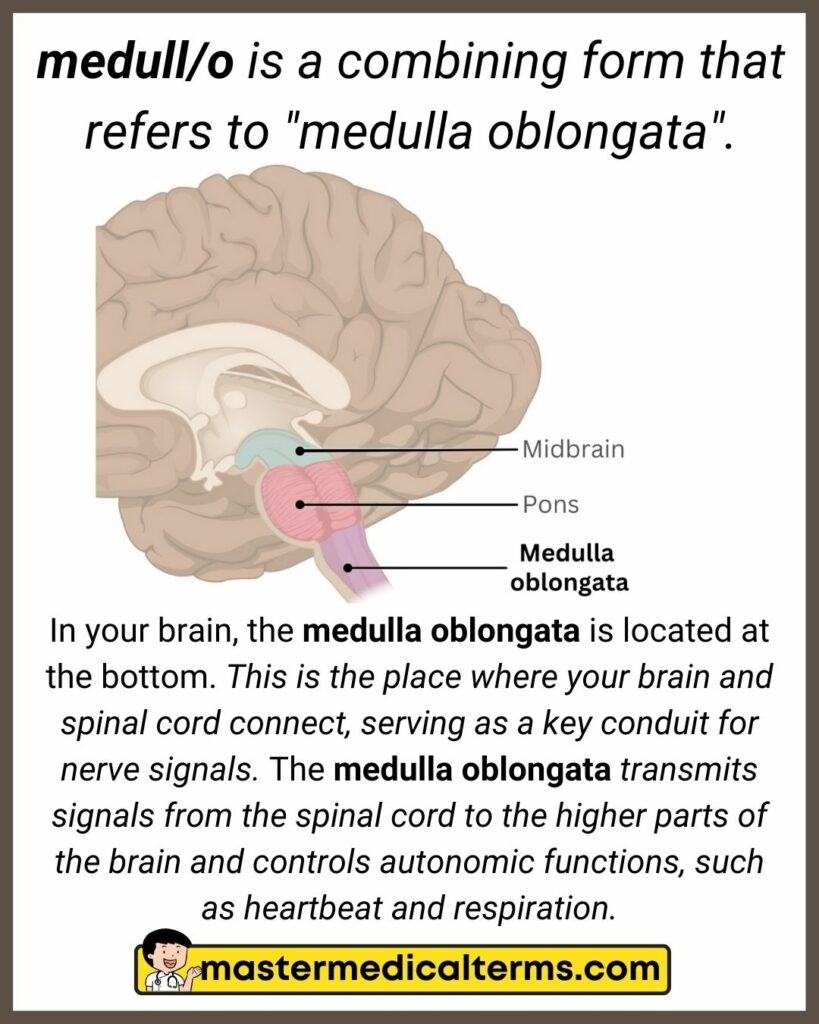

medull/o - Master Medical Terms

Medulla oblongata – Lancaster Glossary of Child Development

Medulla Oblongata | Facts, Position In Brain, Summary & Function

Medulla Oblongata

The Medulla | ThinkFirst

Medulla - The Brain and Psychology